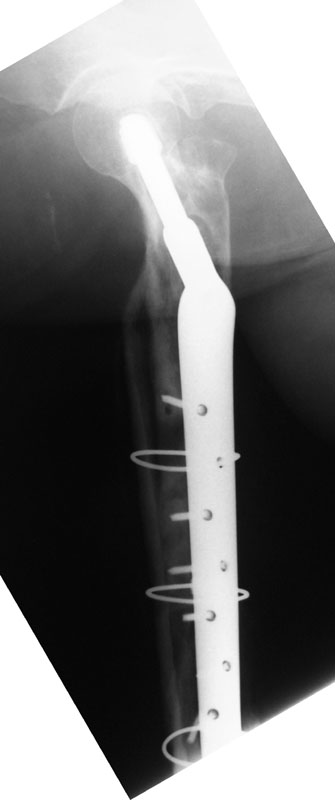

05/28/04 AP

05/28/04 lat

These are the Xrays of a 73 y/o women. The name of each file has the date it was taken and the view. These are all outside films and I know they are limited studies but I think the problem is evident. She had polio at age 5. 20 years ago she had a subtroch fracture plated with a DHS type implant. In Feb, 02 she presented to a local orthopod with a fracture under the plate. The hardware was loose at that time. The local orthopod kept the hardware and cabled allograft to the femur. She did well and was walking with only a cane or occ a walker until last month when she felt something was different and had some pain. She went to her orthopod who took the xrays in May. The orthopod sent her to me then. She has no motors of any significant function below the hip including lacking hip ext and flex. She has mild pain with rotational stress of the femur. She has a thick but not obese leg (she did grow up here in Wisconsin). She wears an AK brace on her leg. She has some pain but it s not too bad. She still can walk but does most of her ambulation with a wheelchair. She has little or no pain in the wheelchair. She is a 1 pack/ smoker for years. She has well controlled hypertension.

I would be interested in your thoughts or questions